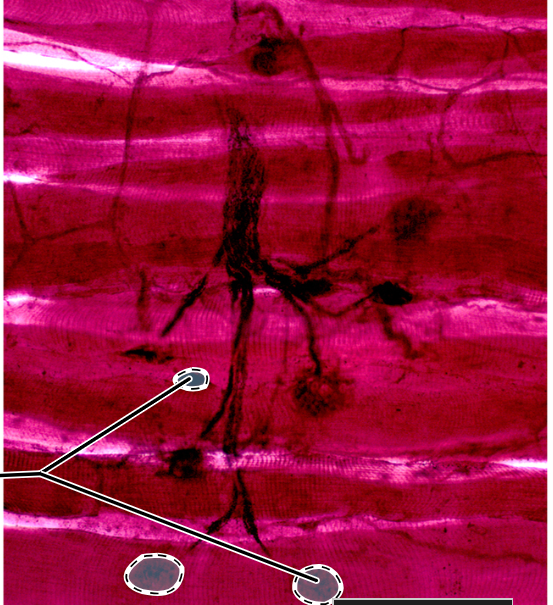

Neuromuscular junction

<p></p>